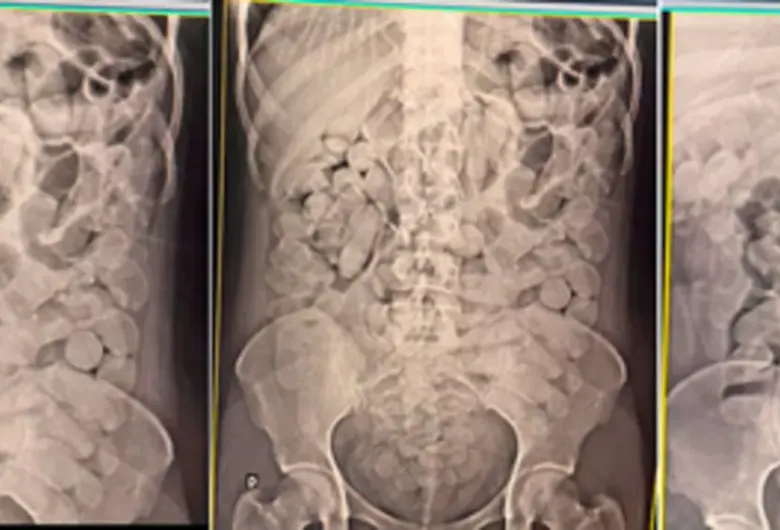

As autoridades relataram que a droga foi encontrada escondida em diversos itens, como palmilhas de tênis esportivos, garrafas de energético, cremes de cabelo e até mesmo em um sutiã. Além disso, quatro mulheres foram levadas ao hospital para expelir cápsulas de droga que haviam engolido.